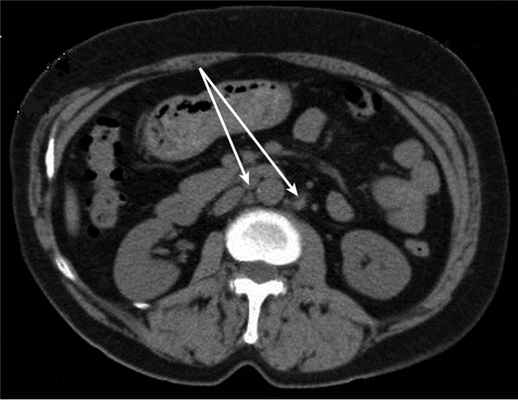

Медиана наблюдения больных основной группы в рамках проспективного исследования составила 15 мес. У одной пациентки 61 года с диагнозом рак эндометрия IIIC стадии рT1cN1Mo через 7 мес после завершения первичного комбинированного лечения диагностирован рецидив заболевания в области забрюшинных лимфатических узлов на уровне отхождения почечных сосудов до 2 см в диаметре (рис. 3). Рисунок 3. Локализация рецидива (стрелки) в забрюшинном пространстве на уровне почечных сосудов у больных основной группы.

На консилиуме принято решение выполнить циторедуктивное хирургическое вмешательство - парааортальную лимфаденэктомию. Морфологически структура опухоли была аналогична первичной неоплазии в матке, представлена низкодифференцированной эндометриоидной аденокарциномой с субтотальным замещением лимфоидной ткани. В послеоперационном периоде проведена дистанционная лучевая терапия с последующей полихимиотерапией. Пациентка жива, находится под наблюдением 2 мес.